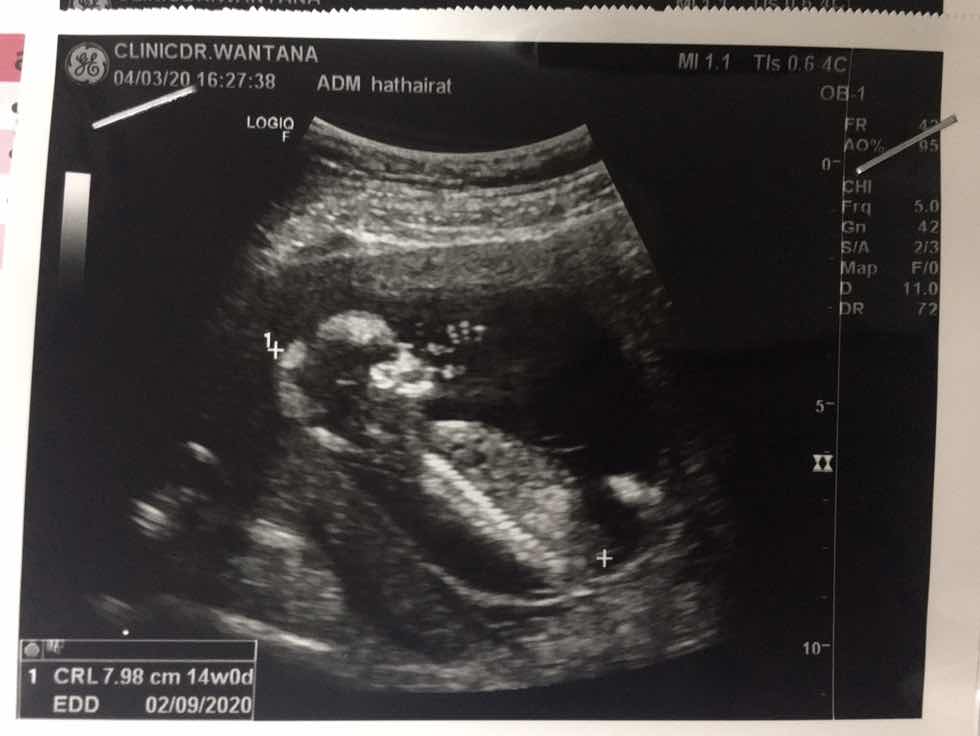

14 วีคค้ะ

14วีค จ้า

14วีกค่ะ